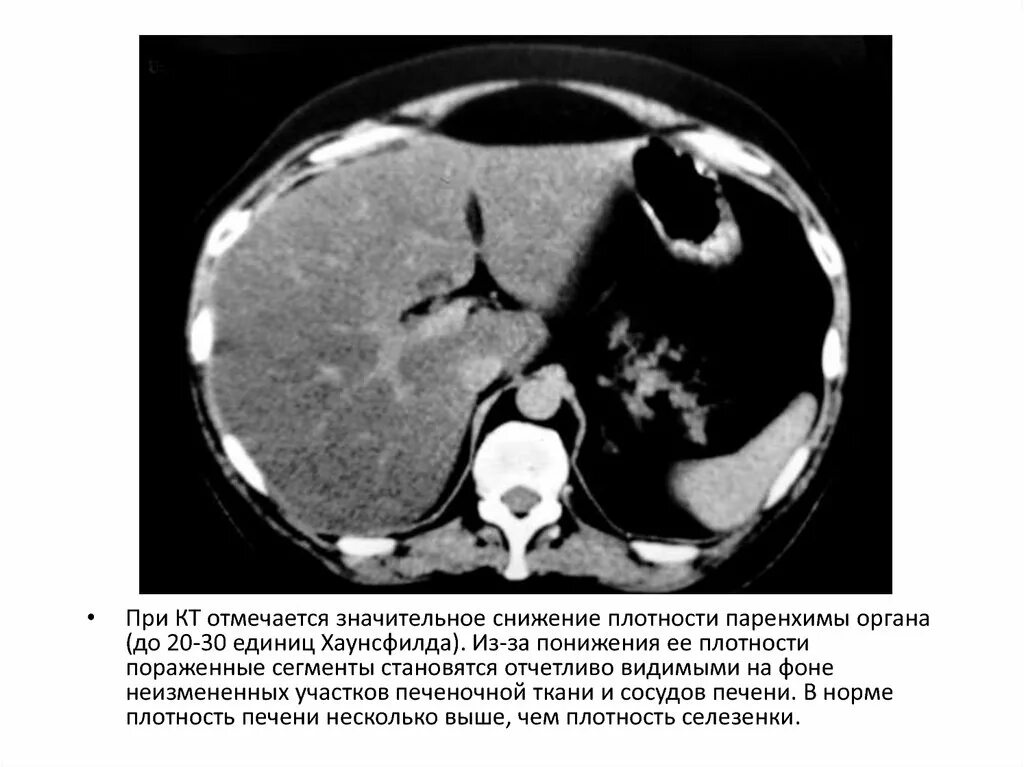

Плотность паренхимы печени снижена что